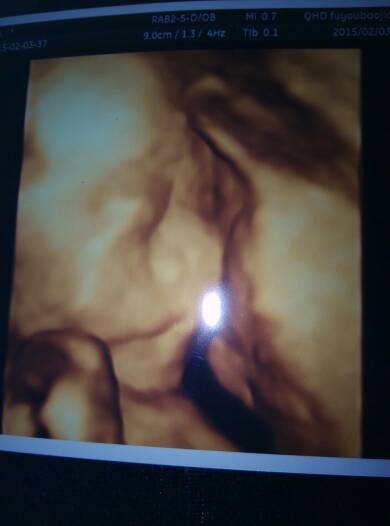

宝妈们今天四维归来了,宝马帮忙看看男女哈 宝妈们今天四维归来了,宝马帮忙看看男女哈, 点击展开 天使_T9gv 2015-02-03 19:13 为您推荐: 其他回答 看着好像是男孩 蜜色遗忘 2015-02-03 22:14 不爱吃也要吃 为了宝宝好 当药也得吃 依晨mama 2015-02-03 20:27 男女都一样阿、平常心 乌溜小妹 2015-02-03 20:21 可以吃点钙片 不然喝点纯牛奶 大骨头汤 啥的 我也不爱吃鸡蛋 依晨mama 2015-02-03 19:38 那怎么办啊 大夫说有事么 依晨mama 2015-02-03 19:35 加载更多 相关问题 bc归来,大家帮忙看看宝宝大小哈!可以看到男女宝宝吗? 急 39周4天产检归来 亲们帮忙看看哈 怀孕23+5 四维彩超归来,帮忙看看是否正常 超声测值:BPD:56mm,HC:212mm